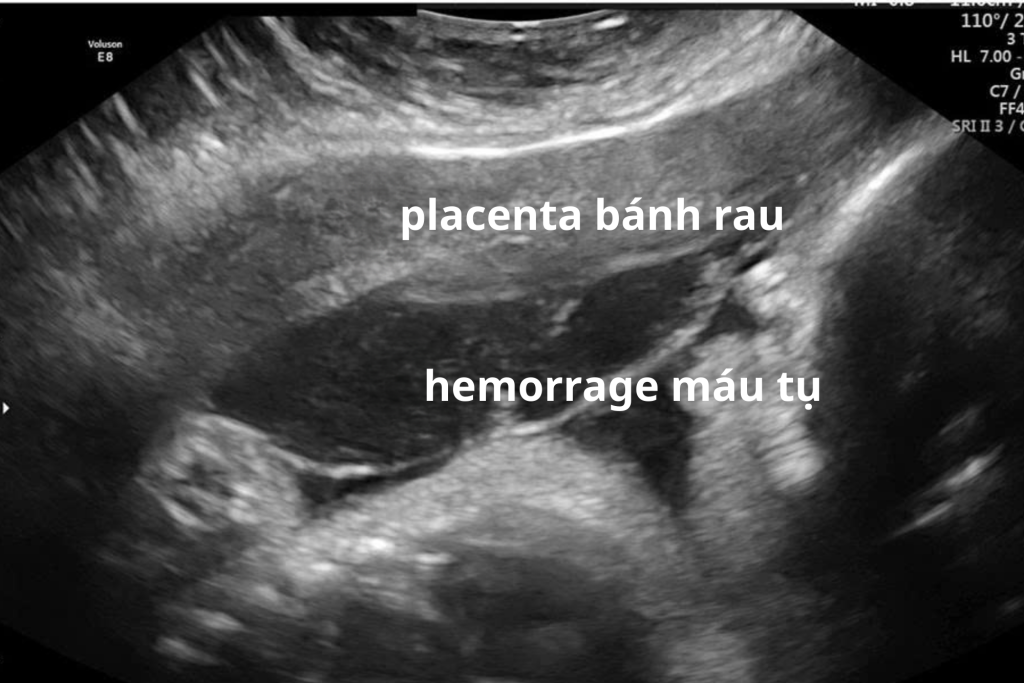

Nhau bong non là tình trạng bánh nhau tách khỏi thành tử cung trước khi thai được sinh ra.

- Máu có thể tụ lại phía sau bánh nhau hoặc chảy ra âm đạo

Siêu âm có thể hỗ trợ phát hiện khối máu tụ sau bánh nhau, nhưng chẩn đoán nhau bong non chủ yếu dựa vào: